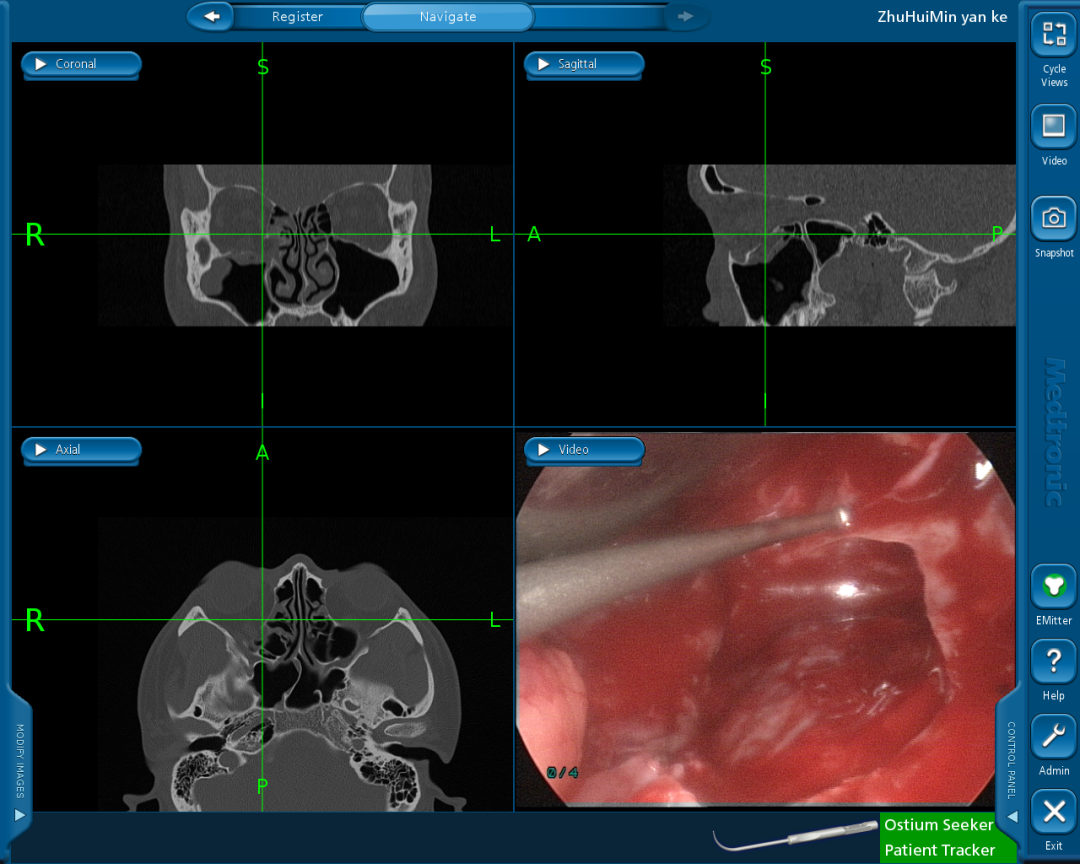

图片

图4.新技术的原理概要

图片图5.应用外科导航系统和内镜辅助分离眶壁缺损区域嵌顿的软组织